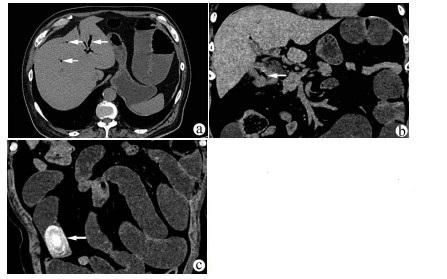

IgG4相关硬化性胆管炎临床特征及诊疗过程分析

李丽, 刘晖, 宋文艳

2021, 37(8): 1883-1887. DOI: 10.3969/j.issn.1001-5256.2021.08.026

摘要(1342) HTML (585) PDF (2114KB)(99)

摘要:

目的  观察IgG4相关硬化性胆管炎临床特点, 并对其诊疗过程进行分析。  方法  回顾性分析2014年1月—2020年9月在首都医科大学附属北京佑安医院诊断为IgG4-SC的25例患者的临床资料,通过电子病例系统采集患者基本信息、病史、诊疗经过、实验室检查、影像、病理资料。分析临床特征、确诊流程、误诊原因等。符合正态分布的计量资料用x ±s表示,非正态分布的计量资料用M(P最小值~P最大值)表示。  结果  25例IgG4-SC患者以男性为多见(21例,84%),平均年龄(57.61±9.73)岁,首发症状常见皮肤黄染和/或尿黄(18例,78.26%)、乏力(9例,39.13%)等。影像学分类:Ⅰ型16例(64%);Ⅱa型0例,Ⅱb型4例(16%);Ⅲ型1例(4%);Ⅳ型4例(16%),合并胰腺受累最多见(22例,88%)。治疗主要以糖皮质激素为主,2周内TBil平均下降67.48%。确诊的22例患者中,门诊拟诊“胆胰系统占位” 15例(68.18%),拟诊“梗阻性黄疸”5例(22.73%)。早期认识IgG4-SC疾病是通过术后病理,随后影像医师逐渐认识,最后通过多学科会诊方式使更多临床医生认识该病,患者得以更早确诊。  结论  对梗阻性黄疸的患者,临床医生需要结合临床表现尤其是影像学特点,对IgG4-SC进行鉴别。影像科、病理科、多学科会诊方式在帮助临床医师认识疾病、确定诊断方面发挥重要作用。